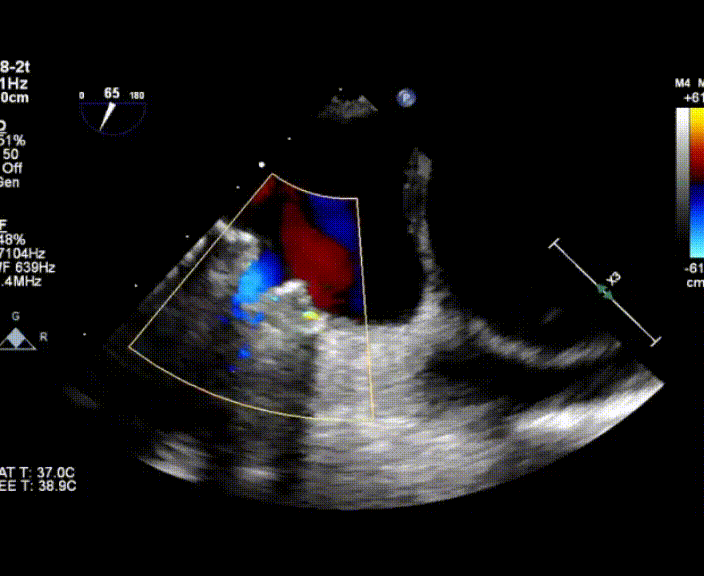

術中首先在局麻下穿刺股動脈、股靜脈,完成心導管檢查評估后轉為全麻,在食道超聲引導下穿刺房間隔,穿刺成功后將加硬導絲送入左上肺靜脈建立軌道,根據(jù)患者病情行球囊預擴張后植入6mm孔徑房間隔造孔支架,經(jīng)透視及食道超聲評估支架左右盤展開良好,夾持于房間隔兩側,固定穩(wěn)定、位置良好,食道彩超顯示房水平右向左為主分流,分流孔直徑符合預期大小,心導管檢查評估達到預期效果,釋放造孔支架。術后12h患者下床活動,恢復順利,擬于近日完善術后評估后出院。

心房分流術是通過器械制造穩(wěn)定可控的心房間分流,適應證包括藥物治療效果不佳的左心衰或肺動脈高壓右心衰。本例患者為肺動脈高壓右心衰,術中成功放置MicroFlux®造孔支架在房間隔理想位置上,創(chuàng)造穩(wěn)定可控的心房間分流(此例患者以右向左分流為主),在不顯著增加左心負擔的情況下,有效降低患者右心房壓力、緩解體循環(huán)淤血,增加左心輸出量,改善患者癥狀、活動耐力和生存質量。同時,國內外也已經(jīng)開展多項房間隔造孔支架在射血分數(shù)保留、射血分數(shù)中間值和射血分數(shù)降低的左心衰患者中的臨床研究,結果顯示對于經(jīng)過充分的規(guī)范化藥物治療后仍控制不佳的患者,心房分流術可改善患者的癥狀及生存質量?! ?/p>